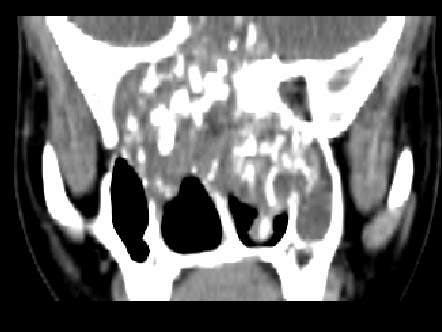

[多选题]男,57岁,睡觉打鼾,近来加重,CT扫描如图所示,正确的描述或诊断是()A.鼻咽腔偏右侧可见类圆形软组织块影B.肿块内密度尚均匀,其上方见较多钙化影C